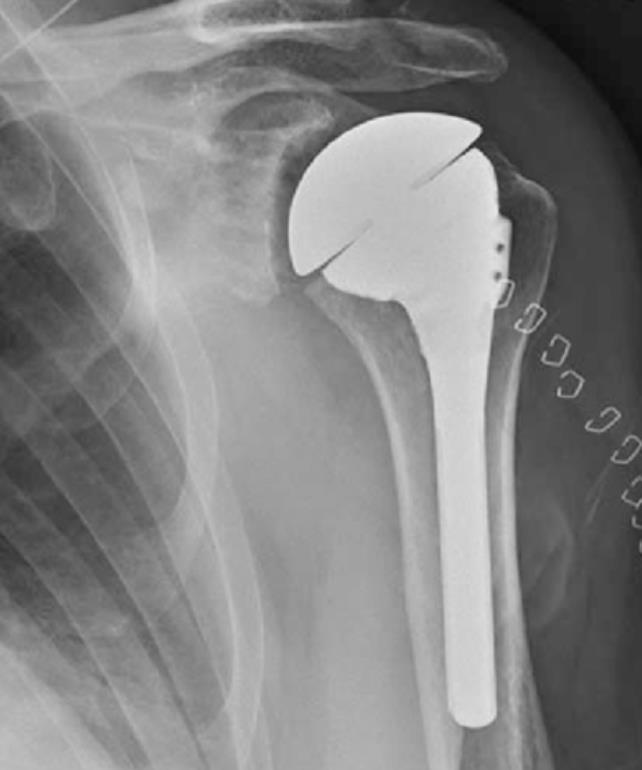

[Blocked from Release] AltiVate Reverse®

• The AltiVate Reverse Shoulder System by Enovis is a reverse shoulder arthroplasty platform designed to restore mobility in patients with rotator cuff deficiency by optimizing implant fit and fixation.

• It uses a lateralized center of rotation and a 135° humeral neck-shaft angle to improve range of motion and reduce complications like scapular notching.

• The system incorporates modular components and precision instrumentation to better match patient anatomy and support stable long-term fixation.